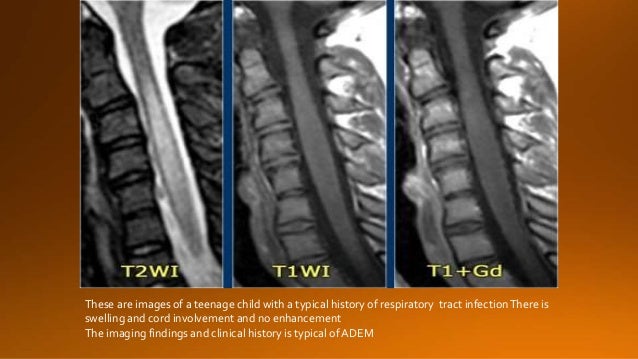

22. 22. These are images of a teenage child with a typical history of respiratory tract infectionThere is swelling and cord involvement and no enhancement The imaging findings and clinical history is typical of ADEM

23. 23. What is typical forADEM and uncommon for MS is: • Massive involvement of the pons. • Involvement of the basal ganglia.

24. 24. The follow up MR shows that the cord has returned to normal again